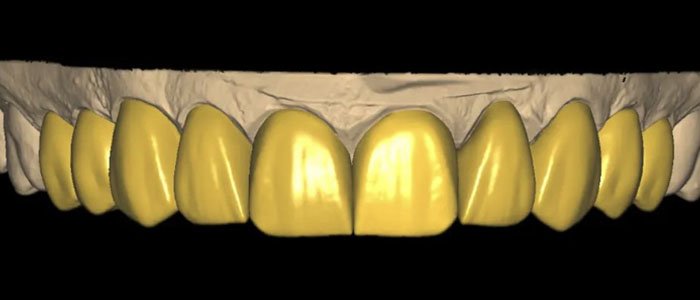

Máxima performance em precisão e qualidade protética. Escaneamento Intra-Oral totalmente digital, massas de moldagem nunca mais.

Aumentar a segurança e otimizar o tempo. O software promove um planejamento de forma digital, unindo as informações para guiar seu tratamento estético.

A impressora 3D, permite que os modelos sejam impressos logo após a consulta trazendo fidelidade e precisão. Além da possibilidade de impressão de provisórios feito na hora, placas e infinitas facilidades clínicas.